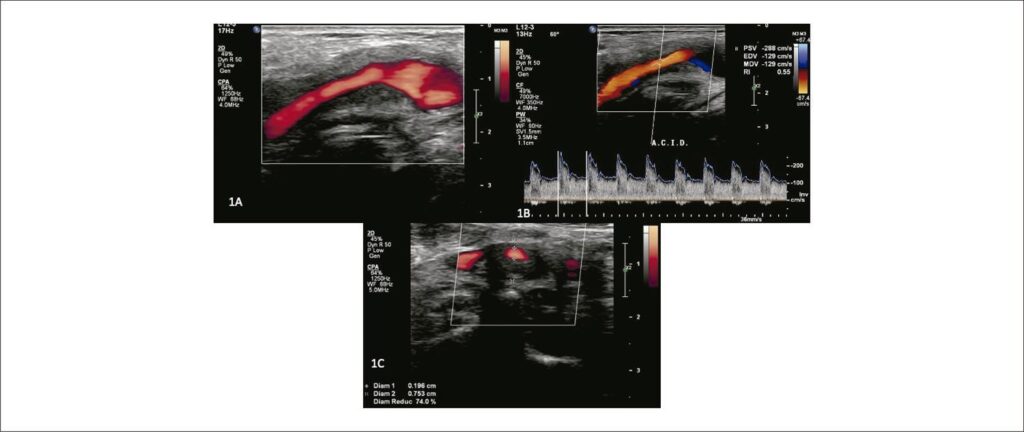

Diante do quadro clínico, foi solicitado um novo exame de USV que incluiu o protocolo padrão de avaliação das artérias carótidas comuns (ACC), externas (ACE) e internas (ACI) extracranianas. Atenção especial foi dada aos tecidos extracarotídeos (perivasculares), devido ao passado de radioterapia. A USV demonstrou ao modo B, extenso acometimento hipoecogênico e homogêneo dos tecidos, englobando a parede arterial na altura da bifurcação carotídea, expandindo-se para a ACI proximal (). A velocidade de pico sistólico e a velocidade diastólica final (VPS/VDF) encontravam-se elevadas: VPS/VDF = 288/129 cm/s (). A estenose local medida no plano transversal da imagem foi estimada em 74% (), compatível com os dados de velocidade do Doppler. A extensão da área acometida foi de 5,57 mm em comparação com um lúmen de 1,96 mm. A ressonância magnética e a angioressonância (RNM, ARNM) mostraram espessamento irregular, com realce pelo contraste, na ACI proximal e bifurcação, corroborando com os achados da USV ().